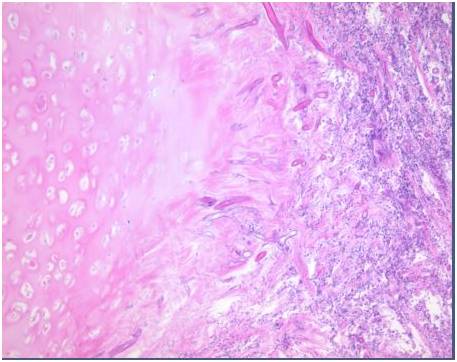

【病理表现】

气道侵袭性曲霉病是一种少见的侵袭性曲霉病.其危险因素与IPA相似,临床表现和胸部影像学改变无特异性,故易漏诊或延迟诊断。内镜下表现有一定特征性,黏膜活检发现曲霉侵袭气道壁为确诊的依据。该病的全身治疗同IPA,气道内治疗对改善气道阻塞及呼吸困难十分重要。总体而言,该病预后不佳,宿主因素是决定预后的重要因素。